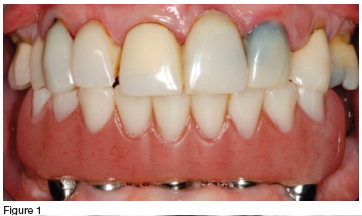

In 2013, a 51-year-old female patient presented with a main complaint of a fractured maxillary provisional bridge spanning from 13-23, pain from the 13, and a worn mandibular implant retained provisional prosthesis (figure 1). The implant-retained prosthesis had been placed in 2009, but no definitive prosthesis was ever made. The patient was adamant that she did not want to lose any more teeth, and neither did she want to wear a removable appliance.

The maxilla had six remaining teeth, pain from the fractured 13 abutment tooth and grade 2 mobility of the 11 (which was expected as it had been serving as a pier abutment tooth in the provisional prosthesis (figure 3). The mandible had a severely worn acrylic hybrid prosthesis retained by five implants (figures 1 & 2).